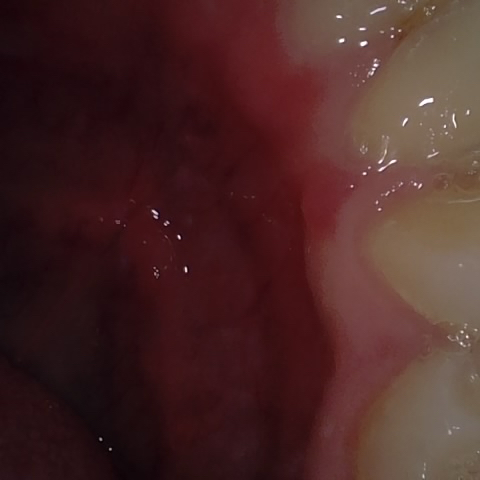

Annotated as "Bad"